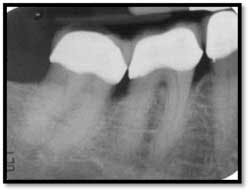

LL Quadrant#27M, now 2mm reduced from 6mm, tissue tight and firm

#26 DF, now 2mm from 8mm

#26 F now 2mm. All tissue is light pink, tight and firm.

Bone fill #26 and 27,no mobility

#18 buccal reflected in a mirror. Now probes 2mm reduced from 9mm

A full set of radiographs taken 13 months post therapy show bone fill in the deepest pockets, with generalized pocket reductions of up to 7mm.